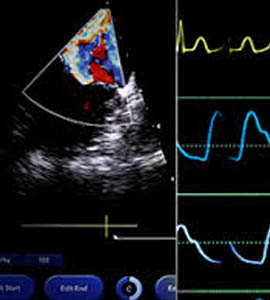

ECHO

An echocardiogram, is a scan used to look at the heart and nearby blood vessels.